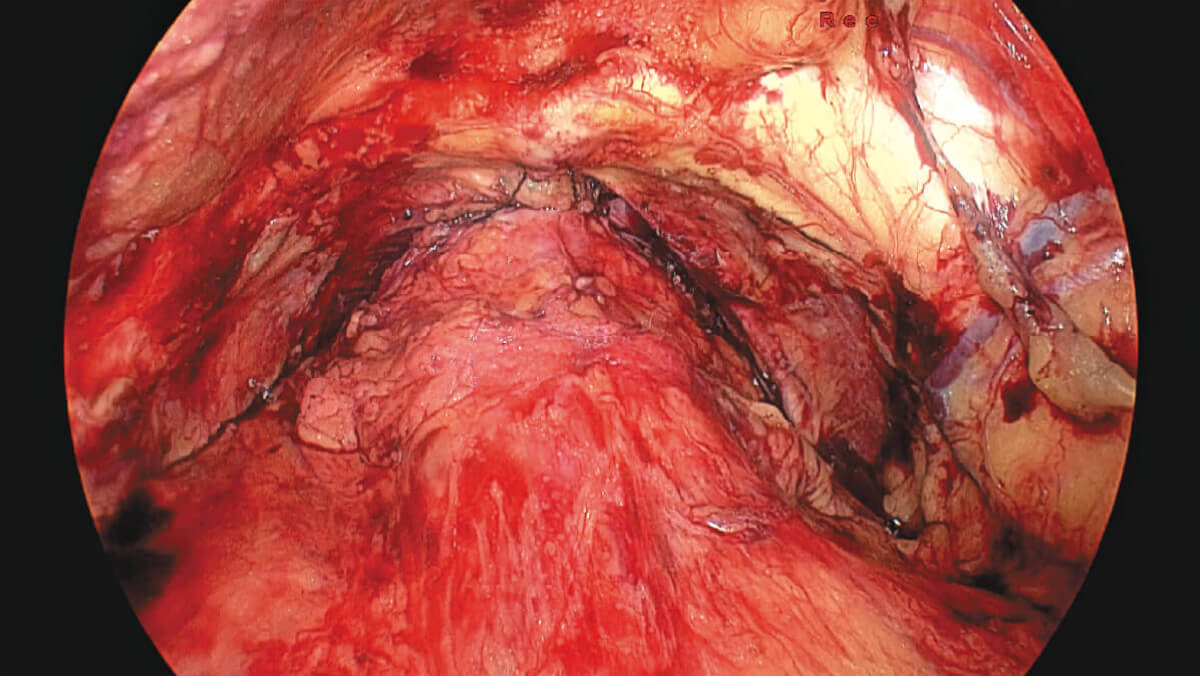

表面细节不遮盖

边界清晰,利于切缘评估

细微结构无伪影

避免术中误伤

荧光信号强弱分明

精准辅助临床决策